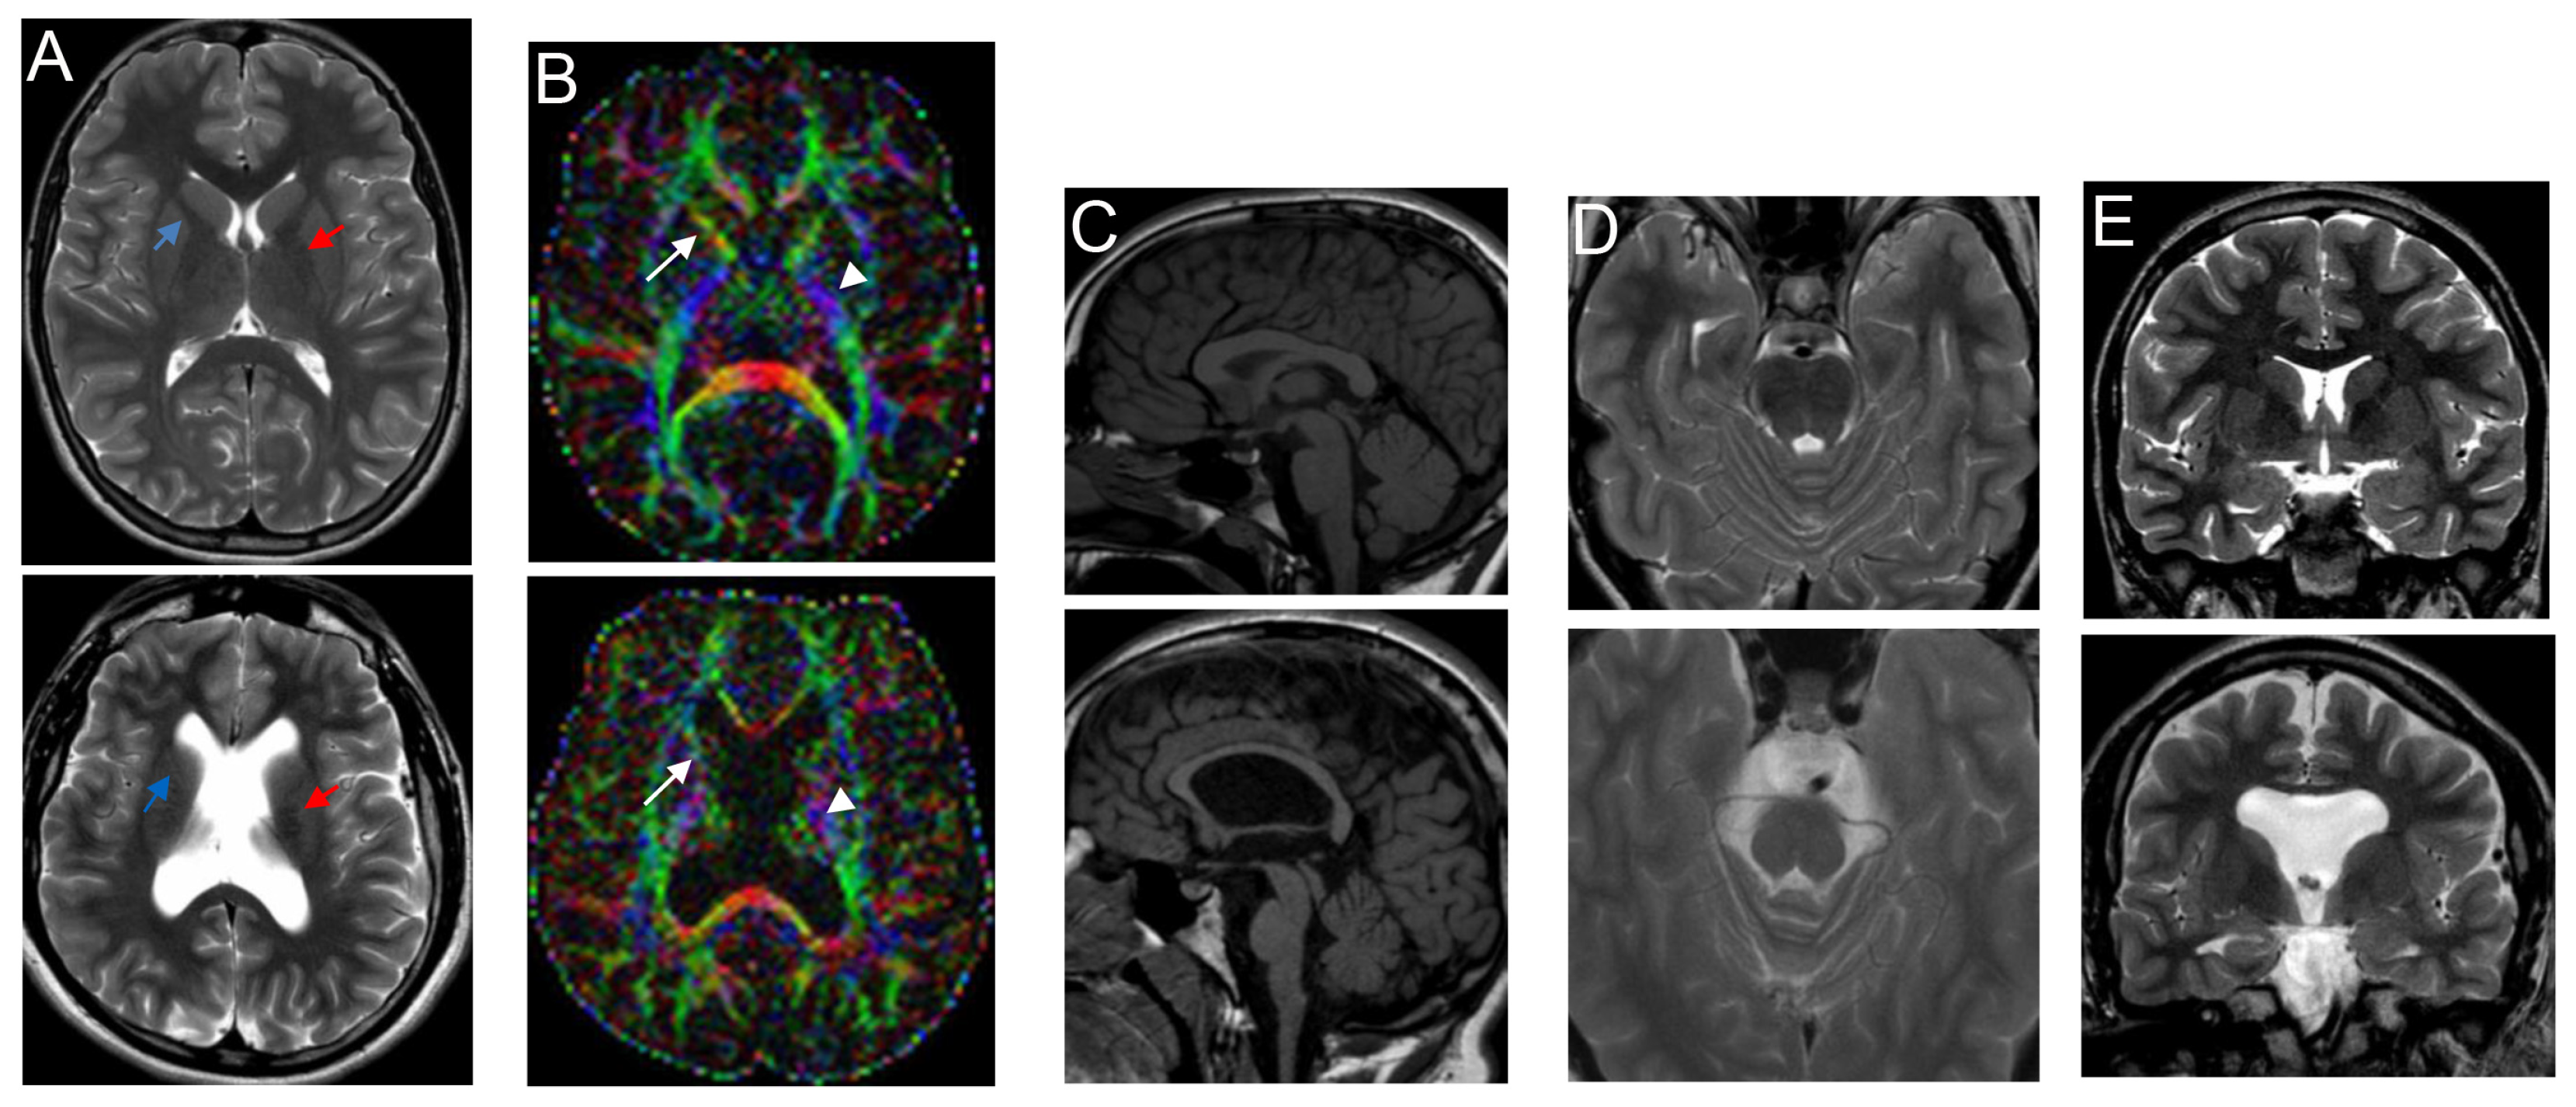

2.2. Brain Imaging

3.2. Genetic Findings

3.3. Spectrum of Brain Malformation in Prenatal Cases and Postnatal Patients Affected by SINO

| c.4144G>T; p.Glu1382* (exon 30) | de novo | Unilateral ventriculomegaly (3rd trimester) | 22 m | Lateral ventricle enlargement, pellucidum septum agenesis, CC hypoplasia, verrticalized hippocampi, thin and dysmorphic brainstem | 18 y M | Monolateral squint, SP | Severe ID; he speaks in sentences | Early-onset macrocephaly, obesity | High forehead | Present study |

| 17 y | Also, dysmorphic and hypoplastic ALIC, partial fusion of lenticular and caudate nuclei, corticospinal tract thinning, optic chiasm hypoplasia, ↓ frontal and temporal lobe volume with cortical gyration simplification, absence of superior cerebellar peduncles decussation | |||||||||